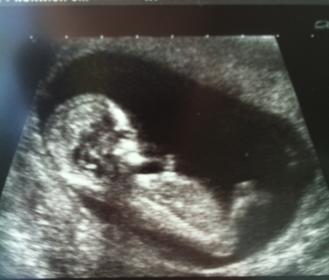

Scan was today and really couldn't work it out.

New to this and don't know what I am looking for.

There seemed to be a long flat white line parallel to the spine, but it didn't show up in the photo.

This was the only picture I was given.... Any guesses?